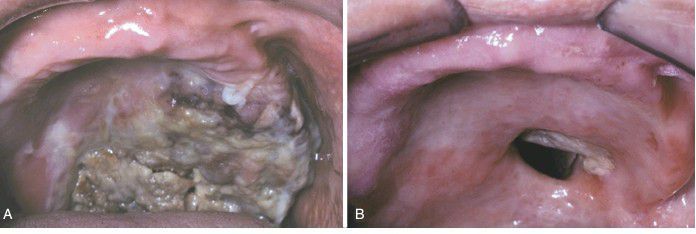

Extranodal NK/T-Cell Lymphoma, Nasal-Type

A, This 62-year-old man had a destructive palatal lesion that proved to be a T-cell lymphoma, and evaluation showed cervical lymph node involvement as well. B, Resolution of the lesion 1 month later, after multiagent chemotherapy.